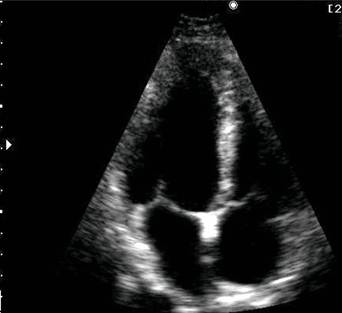

Рис. 7. Эхокардиограмма (апикальная позиция, сечение по длинной оси). Обозначения: ПЖ – правый желудочек, ЛЖ – левый желудочек, ЛП – левое предсердие, МЖП – межжелудочковая перегородка, МПП – межпредсердная перегородка, МК – митральный клапан, ТК – трикуспидальный клапан.

Апикальная четырехкамерная позиция позволяет одновременно визуализировать левый и правый желудочки (по их длинным осям), МЖП, левое и правое предсердия, межпредсердную перегородку, а также митральный и трехстворчатый клапаны. Эта позиция используется для исследования левых и правых отделов сердца, количественной оценки сократимогсти левого желудочка.